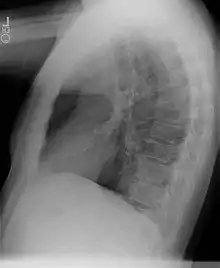

Chest radiograph

• Sequestrations typically appear as a uniformly dense mass within the thoracic cavity or pulmonary parenchyma.

• Recurrent infection can lead to the development of cystic areas within the mass.

• Air-fluid levels due to bronchial communication can be seen.